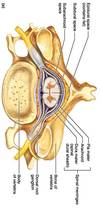

What is the effect of anastetic injected in sacral hiatus?

Only affects spinal nerves not spinal cord

What artery passes through transverse foramen of cervical vertebra?

Exception?

Vertebral artery C1-6 not 7

Direction of superior/inferior articular proceses:

Cervical vertebra

Thoracic vertebra

Lumbar vertebra

Transverse plane

Frontal plane

Saggital plane